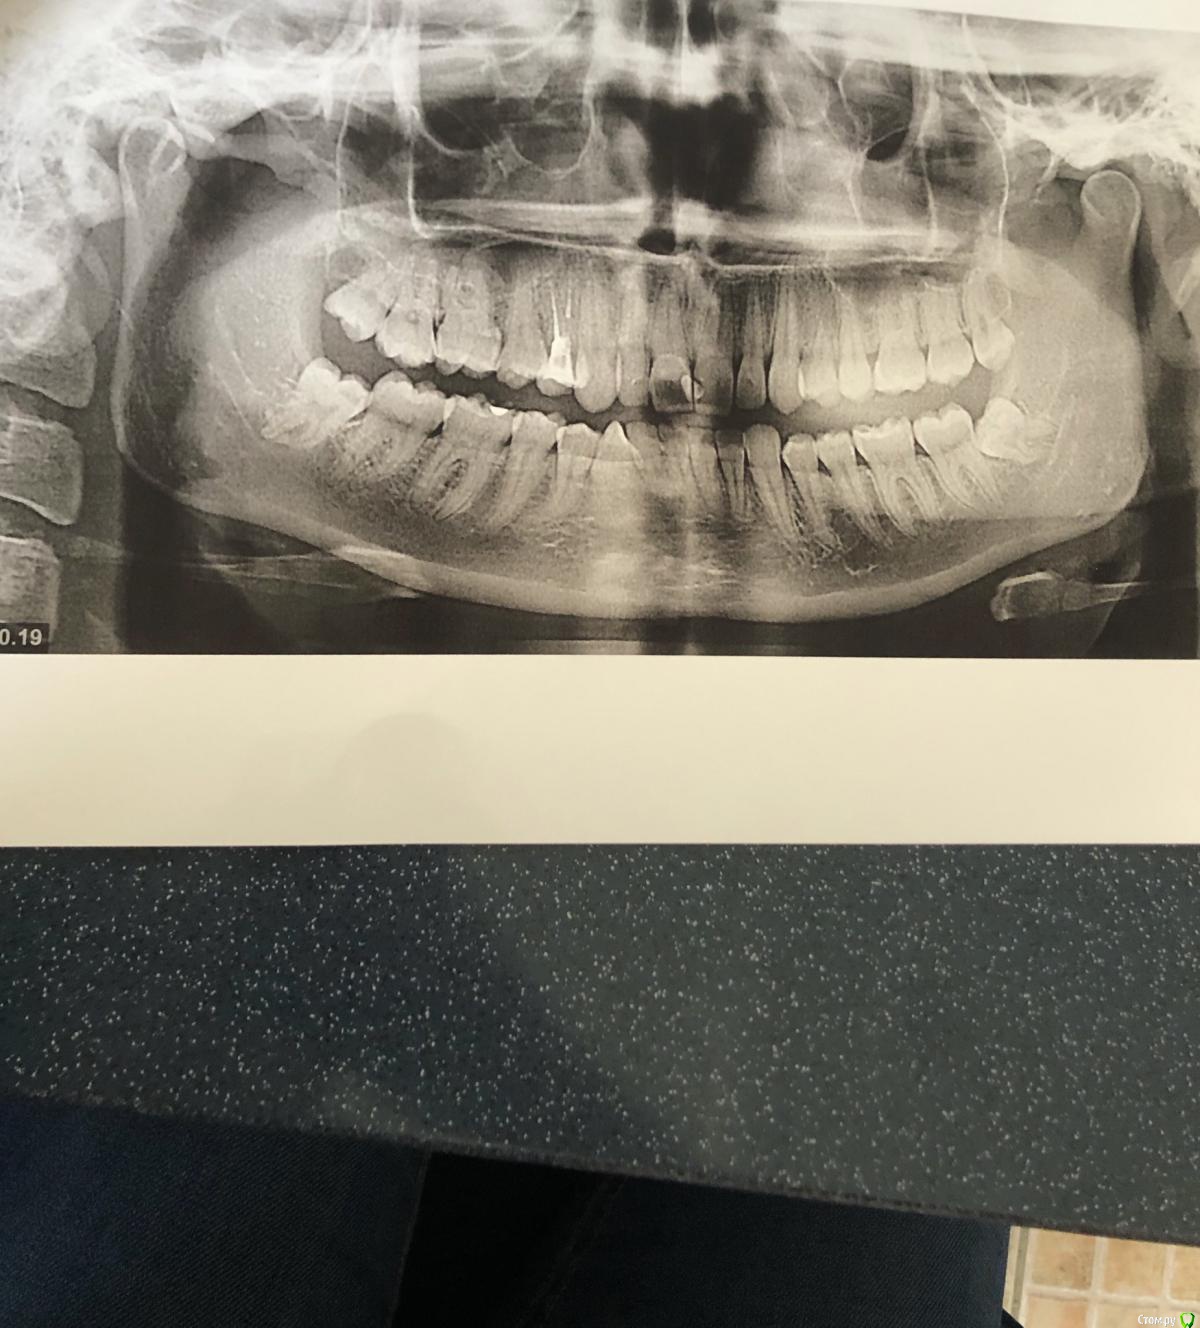

Irouil Опубликовано 3 ноября, 2019 Поделиться Опубликовано 3 ноября, 2019 Может. Если хотите что-то конкретное - сначала ортопантомограмму предоставьте Ссылка на комментарий

Triple_rose Опубликовано 3 ноября, 2019 Автор Поделиться Опубликовано 3 ноября, 2019 (изменено) Может. Если хотите что-то конкретное - сначала ортопантомограмму предоставьтеЕсть такая, сделанная перед операцией Изменено 3 ноября, 2019 пользователем Triple_rose Ссылка на комментарий

red_butler Опубликовано 6 ноября, 2019 Поделиться Опубликовано 6 ноября, 2019 Сделайте панорамный снимок Ссылка на комментарий

Triple_rose Опубликовано 6 ноября, 2019 Автор Поделиться Опубликовано 6 ноября, 2019 А на первом снимке видно, что у меня какой-то дефект этого ВНЧС? Ссылка на комментарий

red_butler Опубликовано 7 ноября, 2019 Поделиться Опубликовано 7 ноября, 2019 А на первом снимке видно, что у меня какой-то дефект этого ВНЧС?ОПГ нельзя использовать для диагностику сустава Ссылка на комментарий

Irouil Опубликовано 7 ноября, 2019 Поделиться Опубликовано 7 ноября, 2019 Я по-другому не могу. Пыталась не пить, но сейчас опять выпила кетанов, пульпит теперь жизни не даёт(Я о том, что если приходится принимать всю неделю - заживает плохо. Надо решать вопрос как-то А на первом снимке видно, что у меня какой-то дефект этого ВНЧС?Я просил оптг для того, чтобы исключить перелом челюсти и остатки фрагментов зуба после удаления Ссылка на комментарий

red_butler Опубликовано 7 ноября, 2019 Поделиться Опубликовано 7 ноября, 2019 Я просил оптг для того, чтобы исключить перелом челюсти и остатки фрагментов зуба после удаления я тоже 1 Ссылка на комментарий